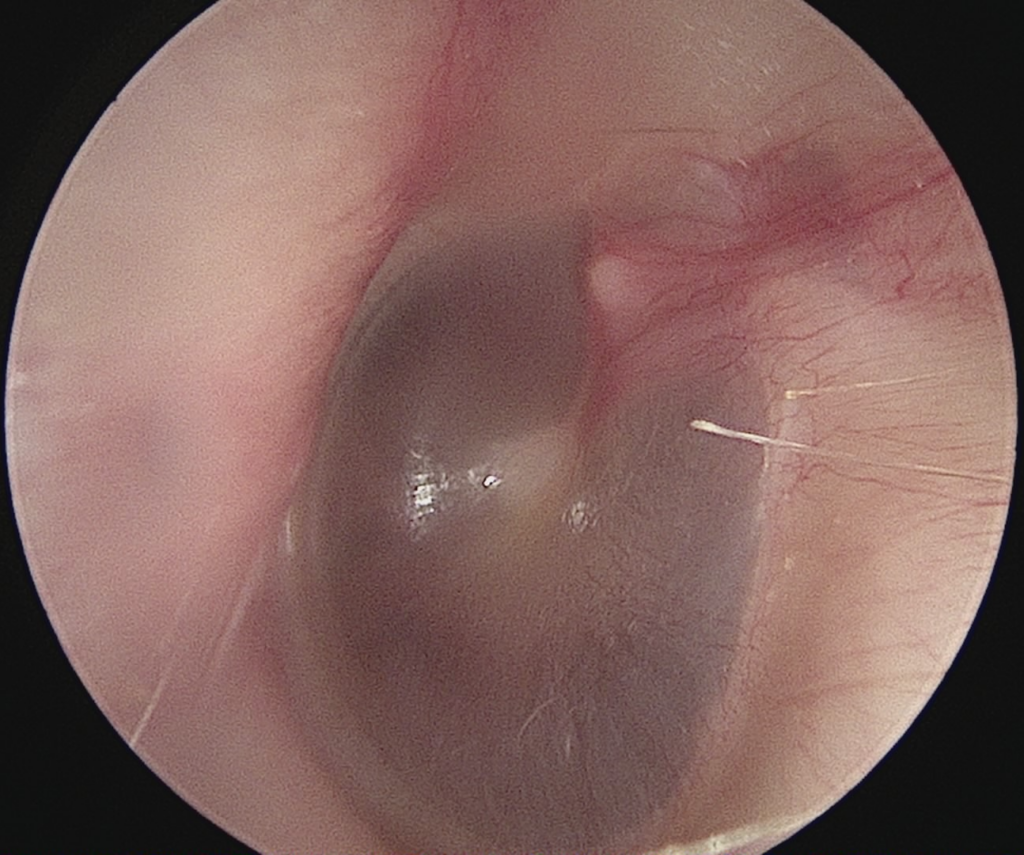

The eardrum should be:

- Clear (partially see-through)

- White/light grey colour

- No holes.